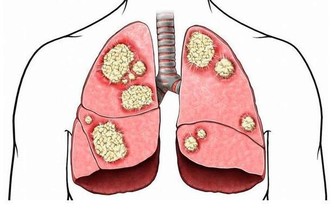

新型冠狀病毒傳染性很強,存在人傳人現象,清潔和消毒一定要做好!